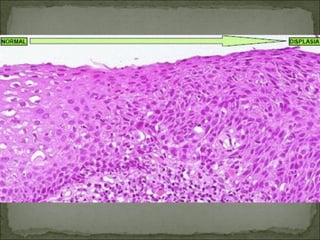

B) Displasia:.-Anormalidad en el aspecto de las

células. Existen diversos grados de acuerdo a

la discariosis, hipercromasia, e irregularidad

nuclear.